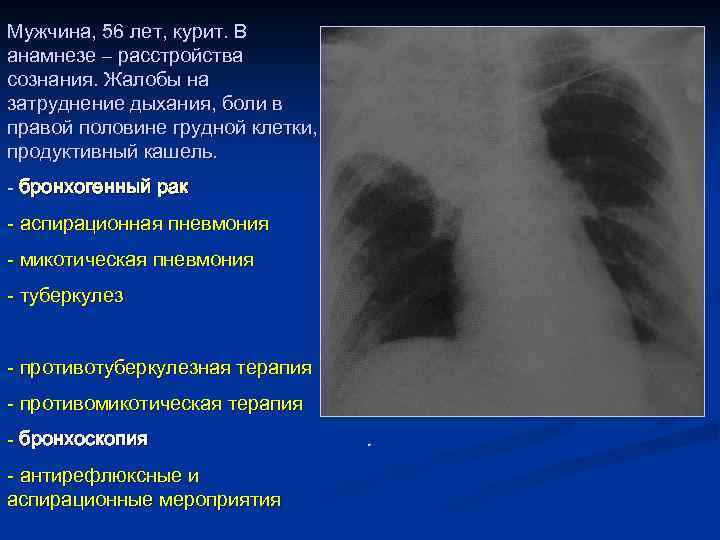

Мужчина, 56 лет, курит. В анамнезе – расстройства сознания. Жалобы на затруднение дыхания, боли в правой половине грудной клетки, продуктивный кашель. - бронхогенный рак - аспирационная пневмония - микотическая пневмония - туберкулез - противотуберкулезная терапия - противомикотическая терапия - бронхоскопия - антирефлюксные и аспирационные мероприятия . Rg - ателектаз